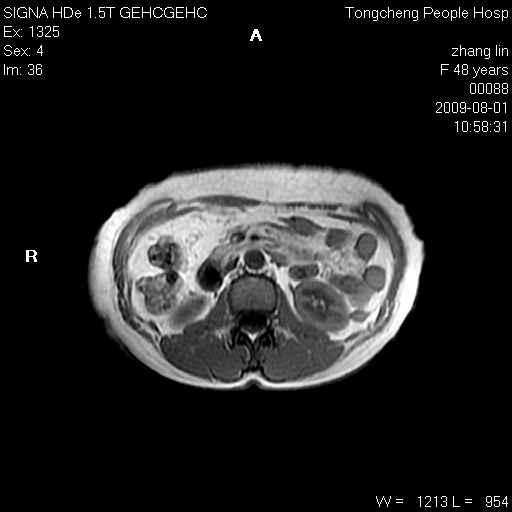

女,48岁。健康体检,彩超发现右肾占位性病变。平素健康。

临床诊断:右肾占位性病变,性质待定(囊肿?肿瘤?)。

上中腹部mr平扫+增强扫描,图像如下:

右肾上极见一类圆形病灶,t1wi呈等信号t2wi呈等高混杂信号,三期增强无强化,边界清---考虑囊肿出血。